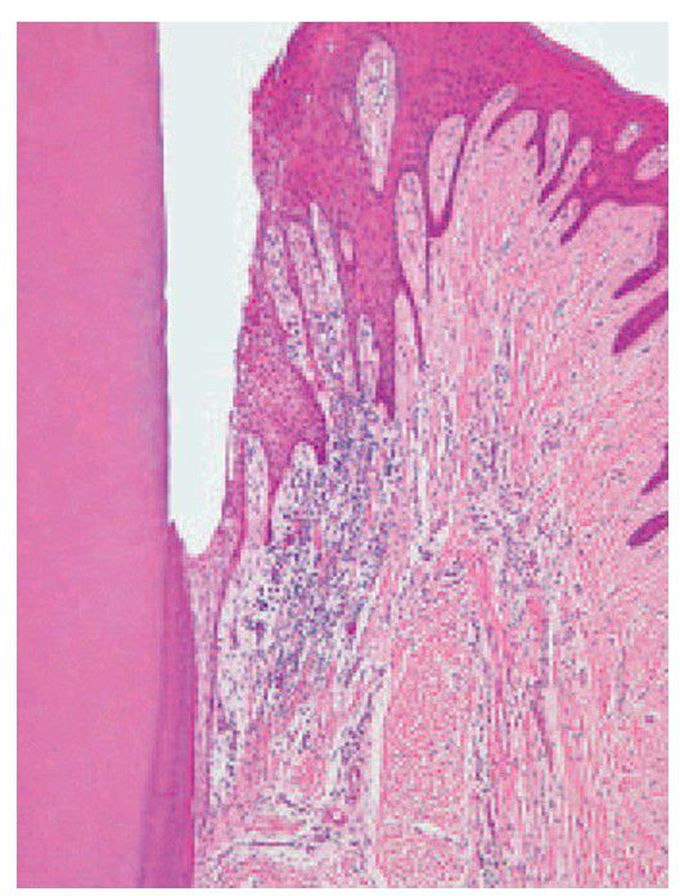

Transition from chronic gingivitis to periodontitis

. No pocket has yet formed but the epithelial attachment has extended on to the cementum and infl ammation has induced epithelial hyperplasia, as evidenced by rete hyperplasia.